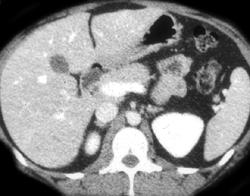

Para-cardiac Nodes